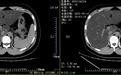

患者的腹部CT提示重度脂肪肝